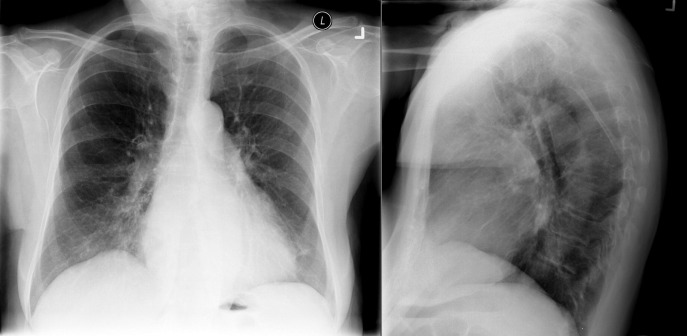

The radiographic findings of mitral stenosis ( Graphic 15-1 ; Figs. 15-1 to 15-16 ) reflect the pressure overload of the left atrium and pulmonary veins, and later of the right heart. As well, the commonly associated chronic atrial fibrillation contributes to (bi)atrial dilation. Associated rheumatic valvular lesions such as mitral regurgitation, tricuspid regurgitation, aortic insufficiency, and aortic stenosis/aortic insufficiency are common, and they alter the appearance of the heart.